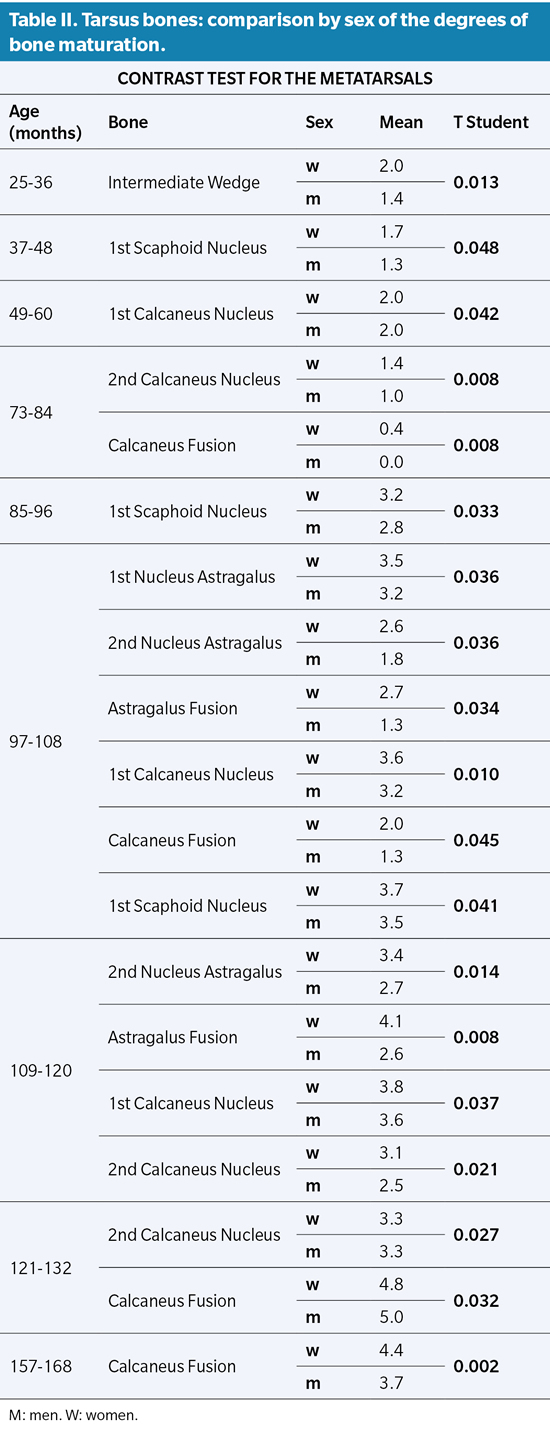

All the bones that make up the Tarsus have statistical significance in the comparison by sex with the exception of the Cuboid, the medial Cuneiform and the lateral Cuneiform. The rest of the tarsus bones have an explicit difference (P value ≤0.05) that translates into a discrepancy between the degree of ossification and its speed, later and slower for males (Table II).

Similarly, the study of the metatarsals shows a delay in ossification of boys with respect to girls. All the ossification nuclei of the Metatarsus are significant, however, it should be noted that the first ossification nucleus of the Metatarsals has a difference by sex greater than 5 to 6 years (61 to 72 months with P value ≤0.011). The same occurs with the ossification of the second metatarsal ossicle between 7 and 8 years (85 to 96 months with P value ≤0.004). The fusions between primary and secondary nuclei have their greatest statistical significance around the mean age interval of 14 to 15 years (169-180 months with P value ≤0.000), where the delay in the rate of ossification in sex becomes more evident. male versus female (Table III).

Our results coincide with what is established in the classical literature regarding the differentiation of bone maturation by sex, confirming that epiphyseal fusions occur earlier in females than in males. In addition, we affirm that this situation occurs not only in bone fusions but also in the appearance of most of the nuclei, both primary and secondary, according to what was established by Seucher4.

Nor is the rate of maturation the same for both sexes. This issue was already mentioned by Robledo without specifying exactly which of the two sexes evolved faster or slower. Based on our results, we are able to affirm that the rate of maturation is slower in boys than in girls6.